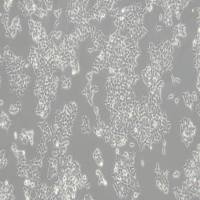

BV-2_小鼠小胶质细胞背景描述:BV-2细胞是由E·Blasi建立于1990年;BV-2细胞由小鼠小神经胶质细胞经逆转录病毒介导转染v-raf/v-myc获永生化。BV-2细胞保留有小神经胶质细胞多种形态、表征和功能特征;免疫组化结果显示,BV-2细胞为MAC1、MAC2阳性;而MAC3、胶质细胞原纤维酸性蛋白、半乳糖脑苷脂为阴性。

生长特性:半贴半悬

细胞形态:上皮细胞样